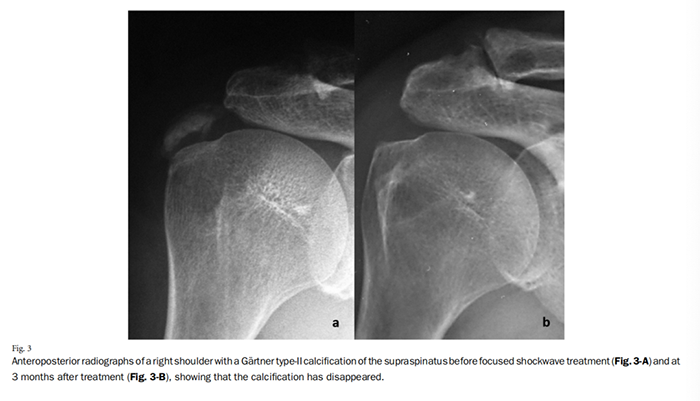

在Gartner I型或II型肩袖钙化病变治疗失败的保守治疗之前,ESWT已作为一种替代疗法出现,用于侵入性手术的前期治疗(图3)。不同作者报道的吸收成功率范围非常广泛

Gerdesmeyer等在一项包括144名患者的多中心随机对照试验(RCT)中,报道了与安慰剂相比,接受低能量和高能量F-ESWT治疗的患者在1年后疼痛、肩关节功能和钙吸收方面显著改善,高能量组的改善率为86%,低能量组为37%,安慰剂ESWT组为25%。Cosentino等在一项单盲试验中使用F-ESWT,报告了肩关节功能显著增加、与安慰剂相比疼痛减轻以及6个月内使用F-ESWT的钙吸收率为71%。Hsu等在一项RCT中,87.9%接受高能量F-ESWT治疗的患者获得良好或优秀的疗效。

Cacchio等在6个月的随访中获得了令人惊讶的高吸收率(86.6%完全吸收和13.4%部分吸收);然而,大多数研究认为高能量F-ESWT更可能导致更好的放射学和临床结果。多项系统综述和荟萃分析已经证明高能量F-ESWT是CTS的安全有效治疗。

Rompe等人和Rebuzzi等人分别比较了F-ESWT与开放手术和关节镜手术在CTS中的治疗效果。他们得出结论认为,结果是可比较的,并且当保守治疗失败时,高能量F-ESWT应该是首选,因为它是非侵入性的。

总结起来,考虑到其在疼痛减轻和功能结果、吸收率、安全性、非侵入性、恢复时间缩短和经济效益,我们认为当保守治疗失败时,高能量F-ESWT是CTS的首选治疗方法。